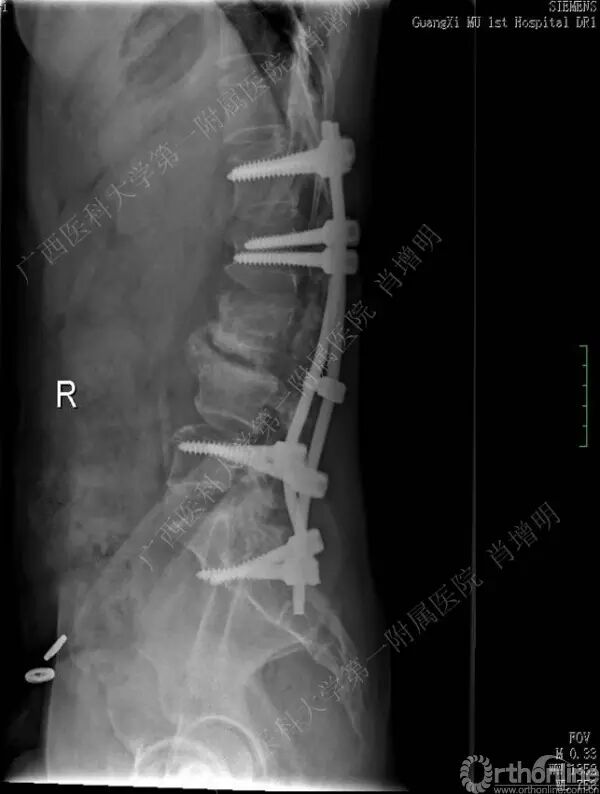

退变性脊柱侧凸是由于椎间盘退变后继发小关节退变,椎管和神经根管容积变化以及脊柱失稳,畸形等病理改变,以疼痛和神经压迫症状为主要表现的常见疾病。

退变性脊柱侧凸多发于50岁以上的中老年群体,是现代常见的老年疾病。多年来,针对该病的临床研究一直没有停步,广西医科大学第一附属医院肖增明教授细致地介绍了该病的诊疗进展。